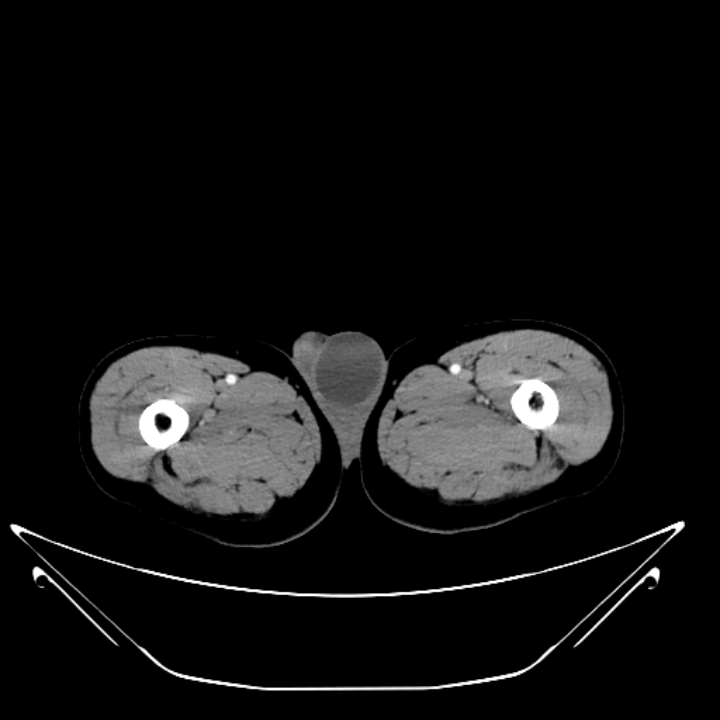

(一)CT 描述:左侧阴囊内见类圆形水样密度影(图 4),大小约 5*4 cm,未见明显强化改变。

CT 提示左侧阴囊囊性灶。

图 4. 左侧阴囊内类圆形水样密度影